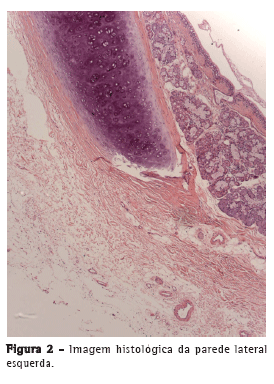

A OCT foi capaz de delinear, em tempo real, microestruturas, tais como epitélio, submucosa, cartilagem e camada adventícia (Figura 1) das paredes anteriores e laterais da traqueia de forma semelhante às imagens histológicas (Figura 2). Na parede posterior, as camadas correspondentes à mucosa, submucosa e musculatura traqueal foram claramente diferenciadas na OCT (Figura 3) e condizentes com a imagem histológica (Figura 4).

A OCT permitiu a identificação, em tempo real, de microestruturas, tais como epitélio, submucosa, cartilagem e camada adventícia nas paredes anteriores e laterais da traqueia. Na parede posterior, foi possível identificar mucosa, submucosa e musculatura traqueal.

Nossos resultados mostraram que a OCT foi capaz de gerar imagens de alta resolução da mucosa, submucosa, cartilagem e camada adventícia traqueais, incluindo microestruturas, como epitélio e pericôndrio, prescindindo de contato entre o cateter e a traqueia, dados esses compatíveis com os da literatura.(5,13)